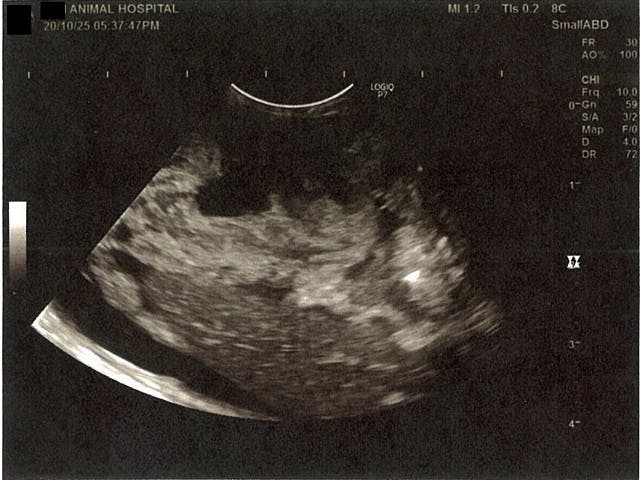

《心臓周りの胸部以外の全ての腹部で腹水がみられるとの診断です》

大網という部分で内臓を包む膜のようなものです。その周りに腹水が溜まっています。

膵臓周りに腹水が確認できるエコー写真

肝臓周りに腹水が確認できるエコー写真